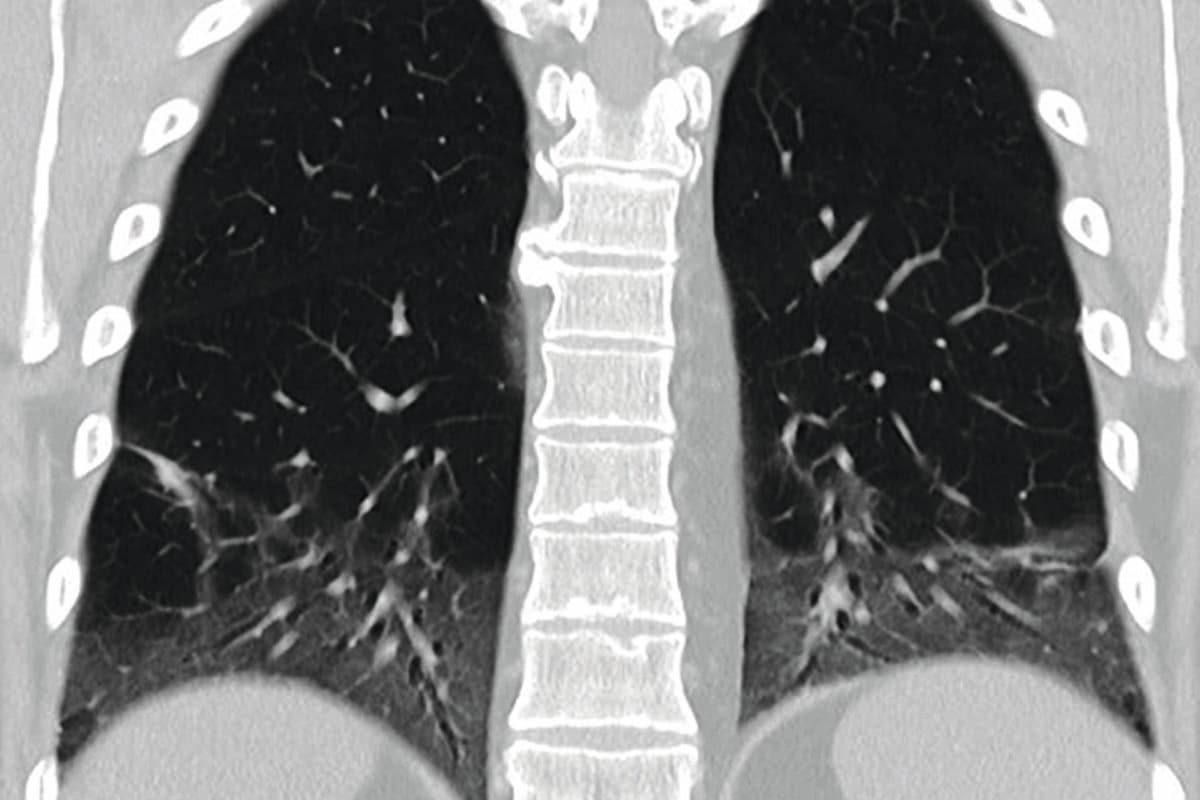

Anhaltende Erschöpfungszustände bei Krebserkrankungen sind eine Tatsache, aber bisher ist die Fatigue bei Kindern und Jugendlichen wenig untersucht. Umso bemerkenswerter ist die aktuelle Studie unter der Leitung des Kinderonkologen Univ.-Prof. Dr. Roman Crazzolara an der Medizinischen Universität Innsbruck.